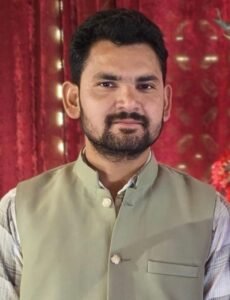

रोगी को लंबे समय से जबड़े में सूजन, दर्द एवं चेहरे के आकार में परिवर्तन की शिकायत थी। विस्तृत परीक्षण एवं रेडियोलॉजिकल जांच के पश्चात यूनिसिस्टिक अमेलोब्लास्टोमा का निदान किया गया। यह ट्यूमर सामान्यतः सौम्य (बेनाइन) होता है, किंतु समय पर उपचार न होने पर यह आसपास की हड्डियों को क्षति पहुंचा सकता है। इस जटिल ऑपरेशन का नेतृत्व दंत विभाग के एसोसिएट प्रोफेसर डॉ. मोहित शर्मा एवं ईएनटी विभाग की असिस्टेंट प्रोफेसर डॉ. मेघा प्रभाकर द्वारा किया गया।